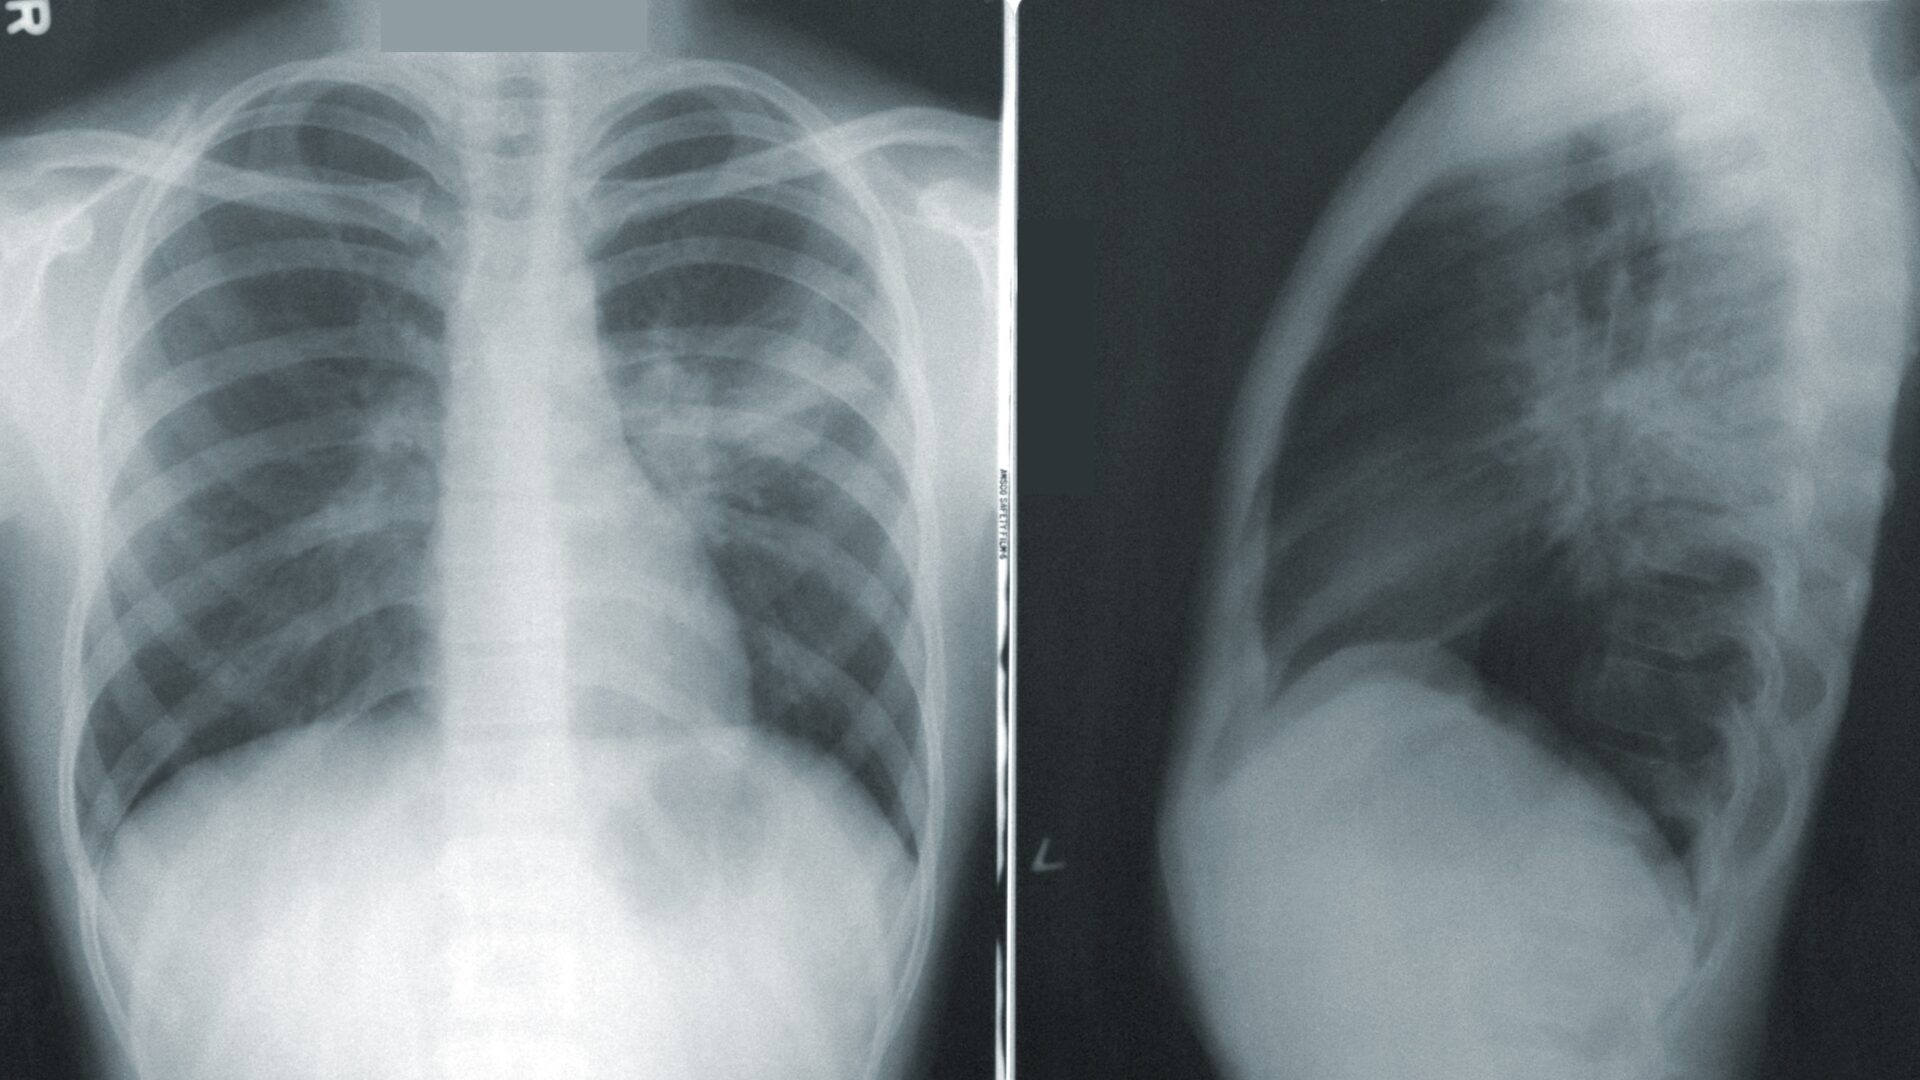

Predicting Survival: Chest X-Rays Provide Vital Insight for Hospitalized COVID-19 Patients June 22, 2023